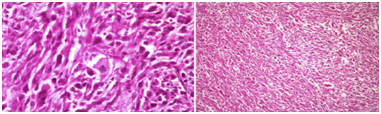

We report a 73-year-old male with UPS . The tumor presented clinically as an enlarging mass in the left breast with a history of one year. There was no history of trauma, nipple discharge, or any other breast lumps. Furthermore, patient had no personal or family history of breast cancer and has never received prior chemotherapy or radiotherapy. The patient had no history of blood transfusion. On physical examination, in the left breast a firm and rounded mass, about 7x7cm diameter, behind the nipple areola complex was palpable. There was no retraction of the overlaying skin and no palpable lymph nodes in the left axillary. Right breast and right axillary were completely normal. Breast ultrasound revealed a solid hypoechoic mass with central necrosiss in the left breast, bilateral axilla were reported as normal. A computer tomography indicated 5x8cm mass with high peripheral vascularity and hypodense necrotic central appearance (Figure 1). In the lower lobes of the left lung, two nodules were observed in the superior and medial basal segments, measuring 7mm and 6mm respectively (Figure 1). There was no pectoral muscle invasion by the mass. Tru-cut biopsy confirmed the pathological diagnosis of UPS and wide excision including nipple areola copmlex was performed (Figure 2). Postoperative course went uneventful. Written informed consent was obtained from the patient. Tissue samples of the primary tumor were taken by the general surgery department. A small piece of the tumor sample and the peripheral blood sample were obtained for genetic study (for FISH and chromosome analysis). The analysises of the FISH and chromosome in cancer and blood samples were performed/done in the genetic laboratory of the Department of Medical Biology and Genetics, Faculty of Medicine, Çukurova University. Standard cytogenetic techniques to detect the blood SCAs were used.

Figure 2 Pathologicalimages of undifferentiated pleomorphic sarcoma (own images of the patient or taken from a publication – clarify and citation if necessary).